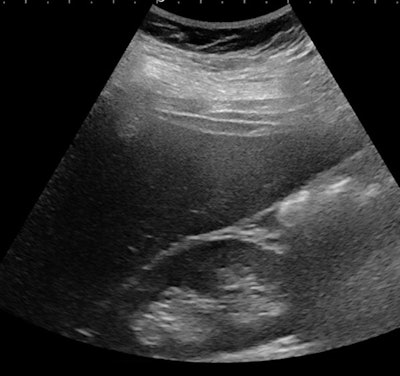

![Échographie d'une jeune fille de 14 ans souffrant d'obésité sévère (indice de masse corporelle [IMC], 42 kg / m2). Il existe une hépatomégalie associée à une augmentation de l'échogénicité hépatique par rapport au rein droit et à une atténuation correspondant à une stéatose sévère. Ci-dessous, le même patient présente une augmentation du ratio foie / reins. Toutes les images avec l'aimable autorisation de Pr Stéphanie Franchi-Abella, PhD.](https://img.auntminnieeurope.com/files/base/smg/all/image/2019/11/ame.2019_10_10_21_09_1189_steatose-fig-1a.png?auto=format%2Ccompress&fit=max&q=70&w=400)

La détection précoce est importante, car le régime alimentaire peut inverser le processus au début de la maladie. Cependant, la détection et la quantification de la teneur en graisse du foie et de la fibrose et de l'inflammation associées, indispensables au diagnostic de la NASH, restent difficiles chez les enfants; L'échographie en mode B reste relativement limitée pour le diagnostic de stéatose hépatique, la teneur en matières grasses devant être supérieure à 20%, mais la quantification n'est pas encore disponible comme outil clinique de routine sur les échographes, selon le Pr Franchi-Abella.